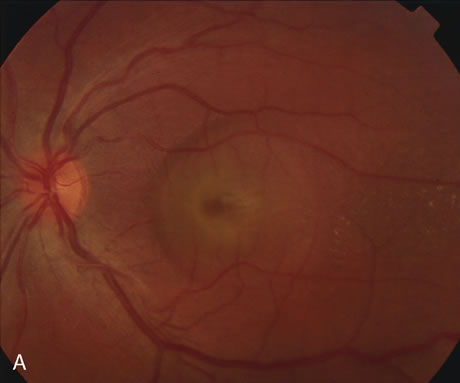

The diagnosis of degenerative myopic maculopathy is clinically obvious. Patients with pathologic myopia are, however, at risk for development of CNV, and FA is helpful in their diagnosis and treatment.251–255 Patients with myopic degeneration have pigmentary changes that can be difficult to distinguish from small neovascular membranes. CNV in pathologic myopia tend to be smaller and less aggressive than the neovascular lesions of age-related macular degeneration.55 CNV in myopic eyes can often be strongly suspected on clinical grounds, using clues such as subretinal blood or lipid exudate, neurosensory elevation, and appearance of a gray membrane visible through atrophic RPE (Fig. 38). FA is sometimes helpful in distinguishing a neurosensory detachment due to a small macular hole from retinal elevation from leaking CNV. FA has been also valuable in demonstrating an association between Fuchs' spots and CNVs254 and in identifying disturbances of choroidal and retinal blood flow in pathologically myopic eyes.255

Fig. 38. Myopic maculopathy with choroidal neovascular membrane. This patient's myopic degeneration is manifested by a large conus around the optic disc and prominence of the choroidal vasculature seen clearly through thinned retinal pigment epithelium. There is a large choroidal neovascularization (CNV) in the papillomacular area. Although CNV formation is common in myopic maculopathy, this lesion is unusually large.